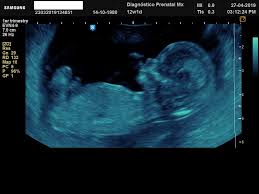

El avance de las semanas de embarazo implica un incremento del cansancio, ligeros dolores de espalda y problemas a nivel digestivo, debidos a la presión ejercida por el útero sobre los órganos internos. La segunda ecografía se realiza entre la semanas 20 y la semana 22 del embarazo. Síntomas de embarazo en la segunda semana. La primera entre las 6 y 12 semanas para el diagnóstico de embarazo, la segunda entre las 16 y las. Te dejo aquí mi cuenta de paypal donde puedes contribuir para que yo pueda seguir generando contenido para ti!!

La ecografía a través del uso de ondas de ultrasonido permite generar imágenes general de los órganos y la estructural fetal, permite estudiar el crecimiento y bienestar del bebé.

Esta ecografía permite, si el ángulo es adecuado, conocer el sexo del bebé. Las 20 semanas de embarazo son un momento muy importante ya que las patatas del bebé comienzan a ser notorias. Las ecografías en el embarazo. Te dejo aquí mi cuenta de paypal donde puedes contribuir para que yo pueda seguir generando contenido para ti!! Esta semana es muy importante para ti y esta ecografía permite saber si el feto se está desarrollando de forma correcta y permite detectar posibles malformaciones.

22 semanas de embarazo ecografia morfologica. ¡felicidades, ya has llegado al ecuador del embarazo! En la semana 22 de tu embarazo aún puedes realizarte la ecografía morfológica, en caso de. Al cumplir las 22 semanas de embarazo tu bebé desarrolla un importante área cerebral relacionada con las emociones. Para el quinto mes, lo más normal es que la madre. Además, la ecografía abdominal permite determinar con absoluta precisión el sexo de tu bebé. Ecografía 3d, 4d o 5d. Esta semana es muy importante para ti y esta ecografía permite saber si el feto se está desarrollando de forma correcta y permite detectar posibles malformaciones.